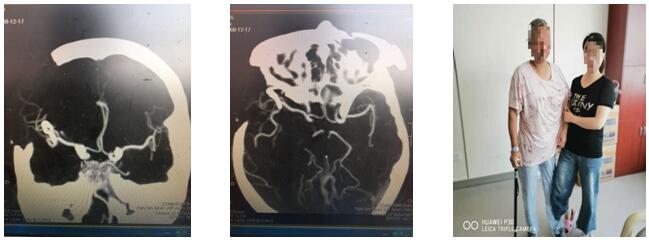

此時患者已經陷入深昏迷,情況緊急,時間就是生命,已經沒有再多的時間考慮了,科主任劉小雷、責任總醫師游文良再次組織全科醫師討論,詳細向家人告知目前情況,最終決定急診開顱手術。如何避免術中發生大出血,成為擺在神經外科二病區團隊面前的最大問題。劉小雷主任,游文良責任總醫師帶領的神經外科團隊經過慎重、反復討論,決定由翼點入路夾閉動脈瘤并清除血腫。手術在全麻下進行。首先要通過腦自然間隙找到大腦中動脈下干,仔細分離,暴露動脈瘤,予以夾閉。整個過程都必須經過腦自然間隙進入顱腦深部,保證腦組織、血管和神經的完好,最后清除血腫,血腫腔嚴密止血。手術圓滿完成。目前患者處于恢復期,患者神志清,言語流利,思維清楚,除左側肢體肌力稍減弱外,其他功能均正常,在家人攙扶下可以慢慢行走。

近年來,延安大學咸陽醫院神經外科二病區劉小雷主任,游文良責任總醫師帶領的神經外科團隊一直致力于顯微血管手術,神經外科顯微手術,微創手術的開展。目前延安大學咸陽醫院神經外科顯微血管外科手術技術已達咸陽市先進水平,此例手術的圓滿完成,標志著我院神經外科顯微外科手術技術踏入新的高度,將更好地為咸陽市及周邊縣區人民服務。